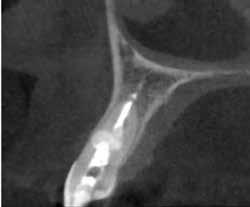

Az elváltozást egy diagnosztikai céllal készített panoráma-röntgenfelvételen észlelték. Az elváltozás kiterjedésének pontos meghatározása, valamint a kezelési terv felállításának és a várható prognózis megítélésének elősegítése érdekében CBCT-felvétel készült (1. a–c ábra). A reszorbtív lézió a fog gyökerének középső harmadában helyezkedett el és a

gyökér meziális felszínét perforálta. A lézió kerek és szimmetrikus volt, amely gyulladásos típusra utalt. Az oszteolitikus terület fókusza a perforáció közelében helyezkedett el (2. ábra). A csontban lévő lézió és a gyökérperforáció az endodonciai kezelés sebészi kiegészítését tette szükségessé. Ennek megfelelően az egy ülésben történő gyökérkezelést követően

1. a–c ábra: Kiindulási CBCT-felvétel. Az axiális síkú metszeten jól látható a gyökér falának perforációja (a); Koronális irányú metszet (b), Saggitális irányú metszet